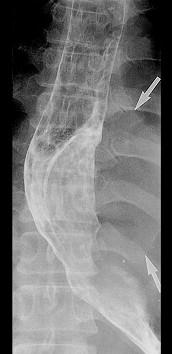

问题 男性患者,32岁,近一年来出现咽下困难、呕吐症状,胸骨后有压迫感,入院行X线钡餐检查,结果如图所示,最有可能的诊断是 ( )

选项 A、食管癌 B、以上均不正确 C、贲门失弛症 D、食管平滑肌瘤 E、食管憩室

答案 D